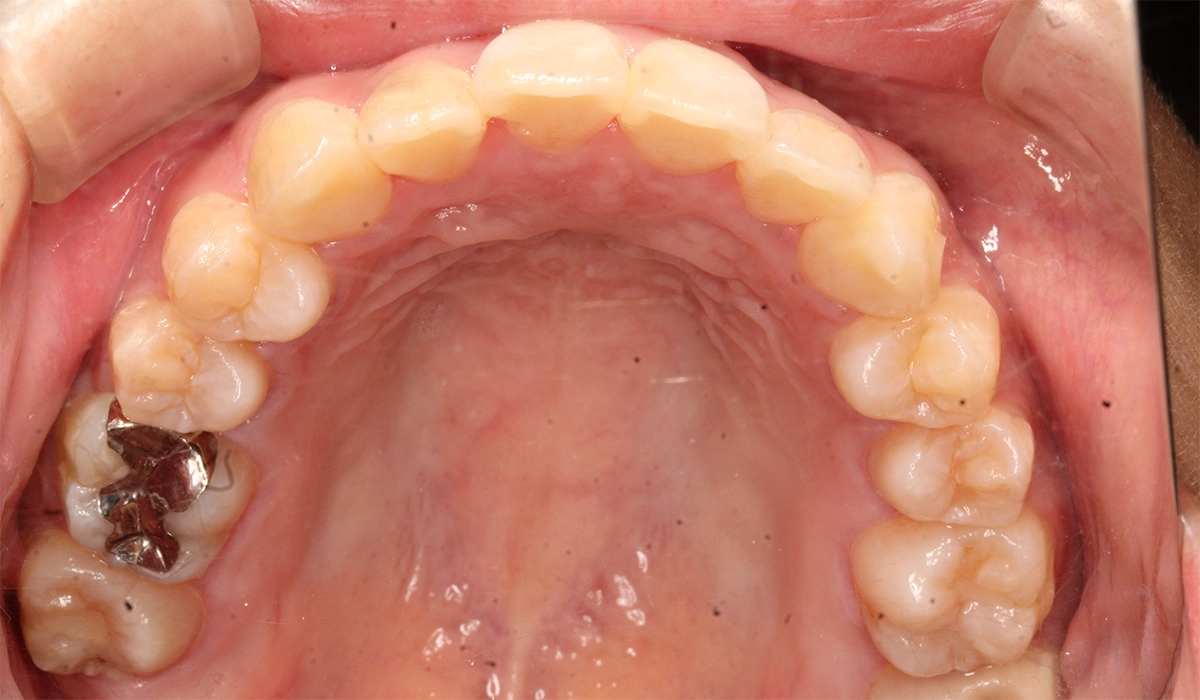

術後:上顎